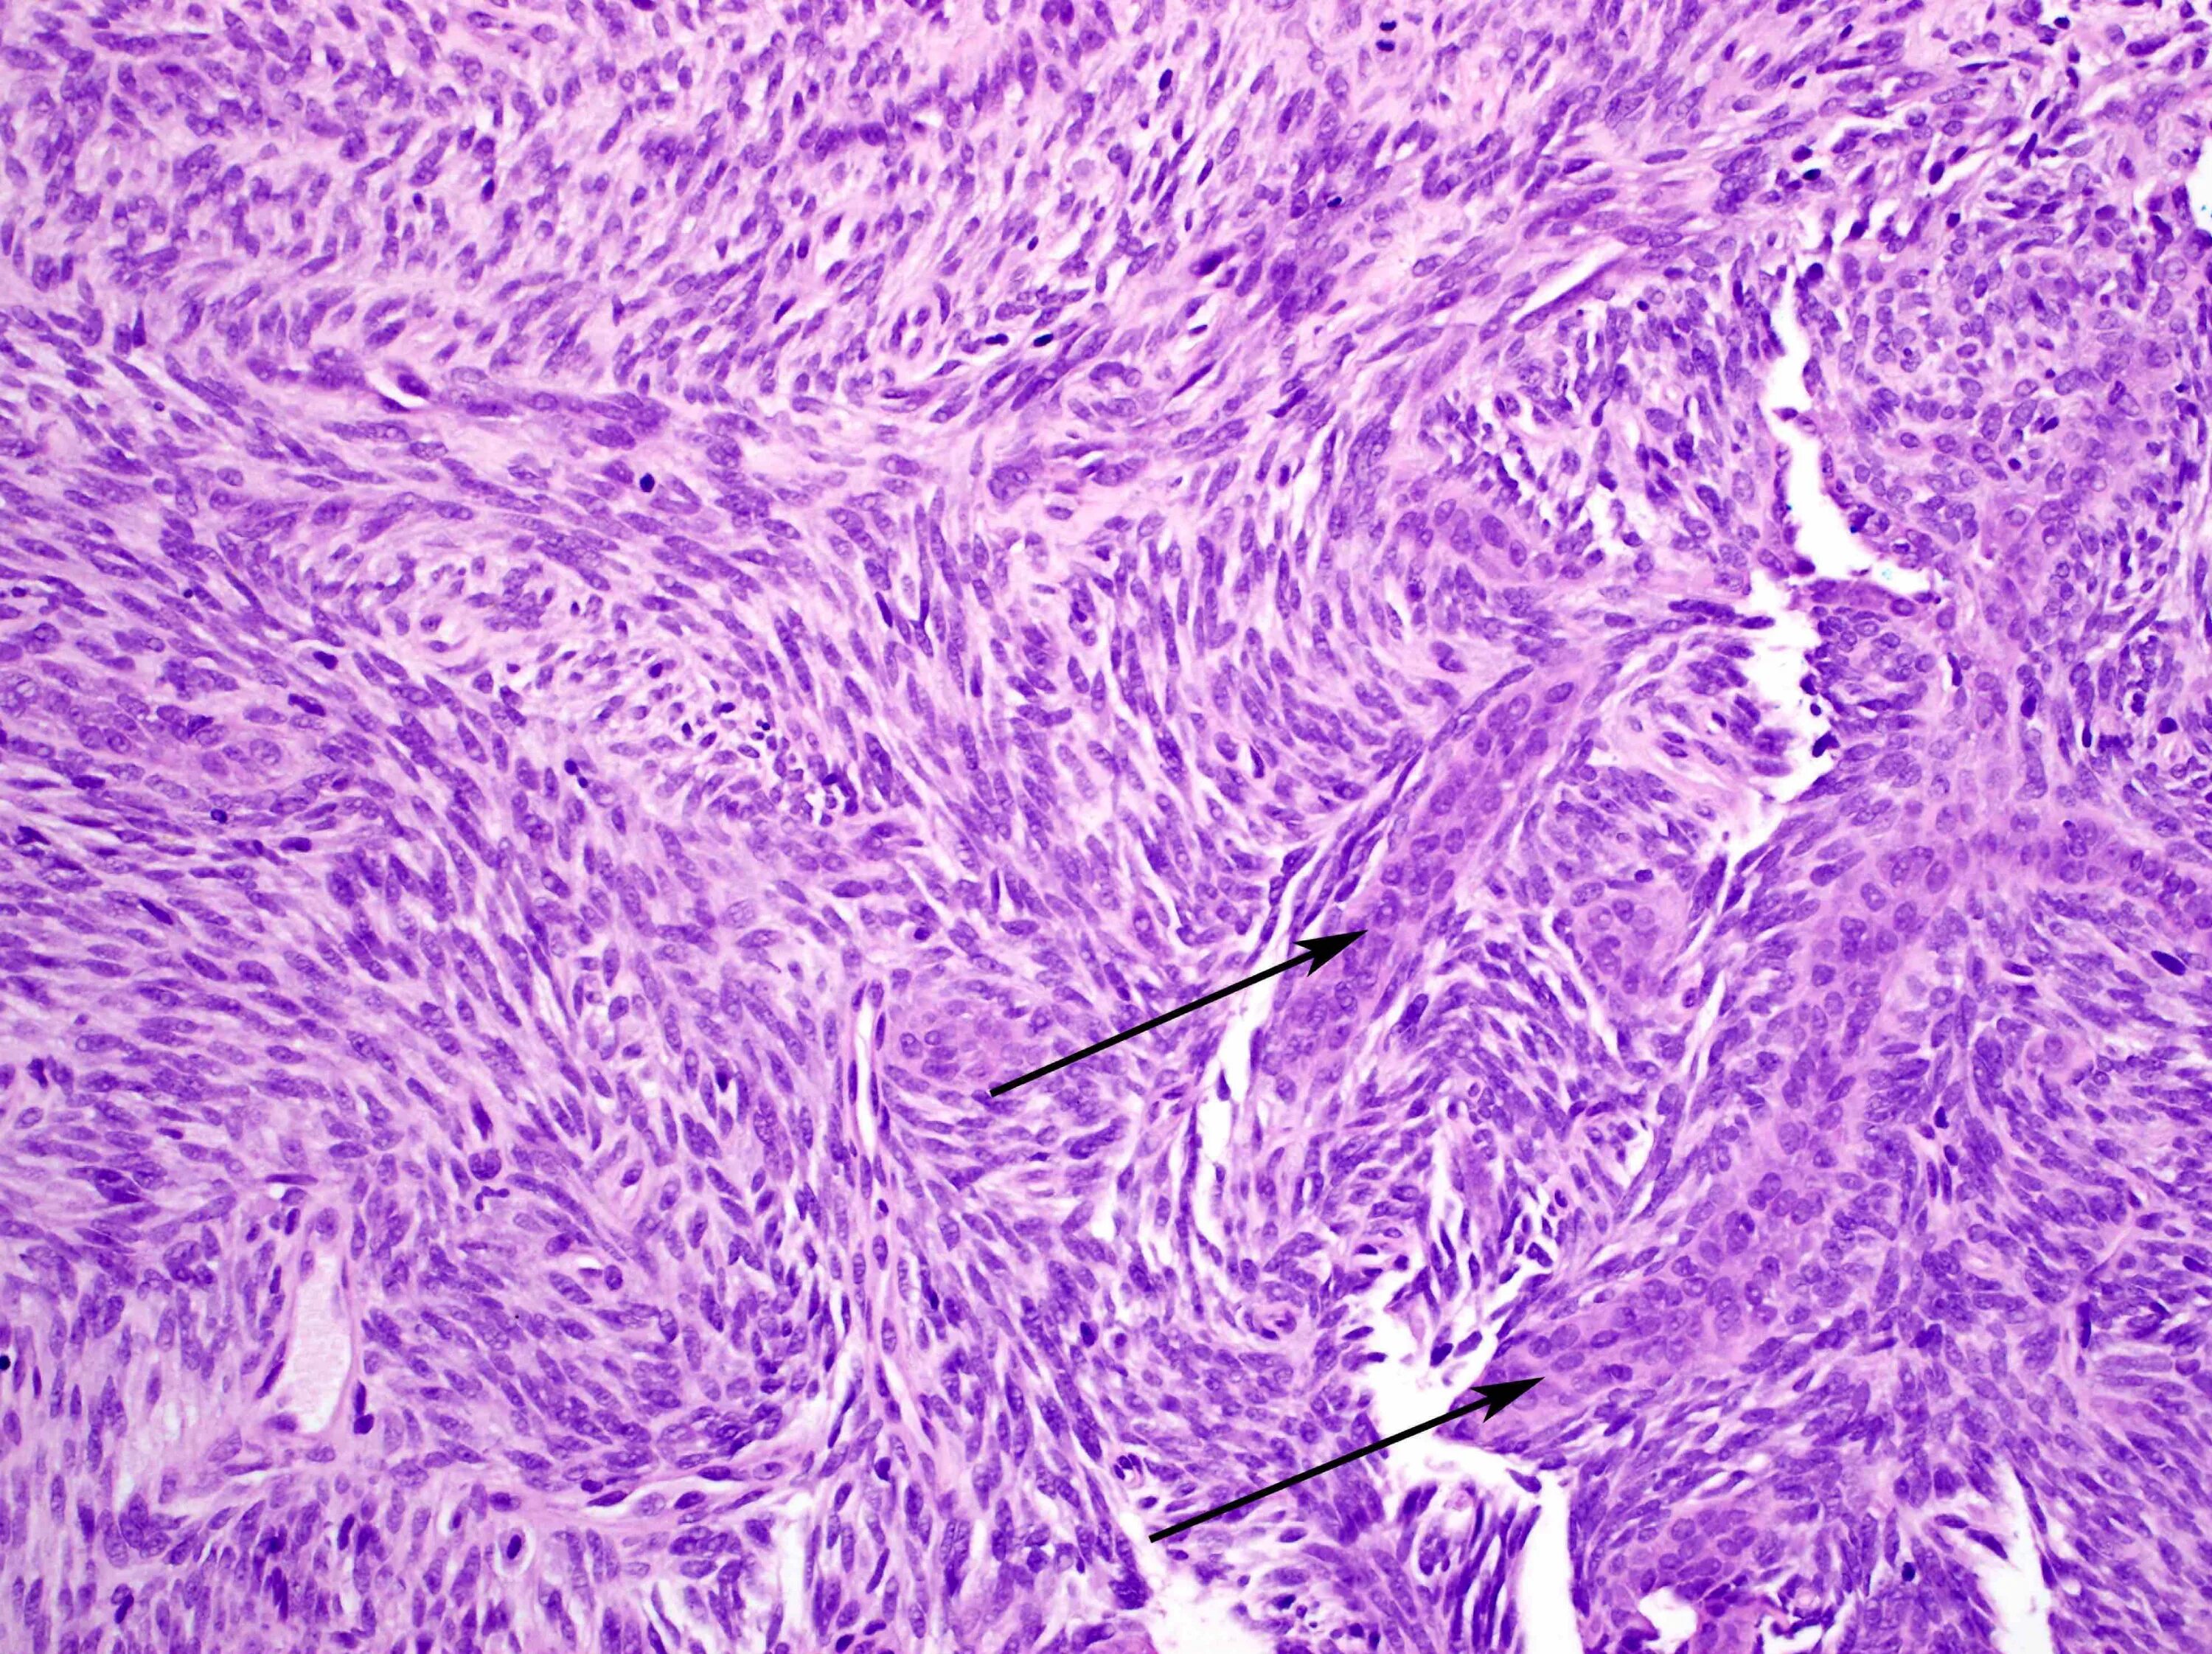

Синовиомы